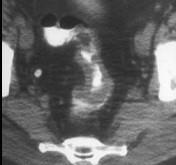

男,53岁,便秘、血便,大便变细,CT如图,应考虑为()A.肠Crohn病B.直肠结核C.溃疡型直肠癌D.慢性溃疡性结肠炎E.直肠淋巴瘤

问题 男,53岁,便秘、血便,大便变细,CT如图,应考虑为()

选项 A.肠Crohn病 B.直肠结核 C.溃疡型直肠癌 D.慢性溃疡性结肠炎 E.直肠淋巴瘤

答案 C